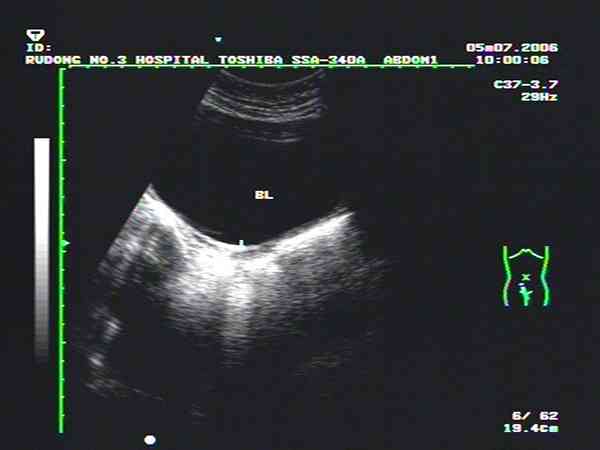

如果確定是基始子宮一般就不會再長大了。按說這個年齡一般乳房、外陰也應該開始發育,目前B超子宮至少是發育不良,建議查一下女性內分泌六項看看是不是發育晚,若是發育晚,那麼就還有可能會重新發育。但是具體能否重新發育因人而異,建議儘快進行治療,治療後看能否隨著青春期進行再次發育。如果青春期過了,或者是已經成年的話,那子宮就不會再發育了。